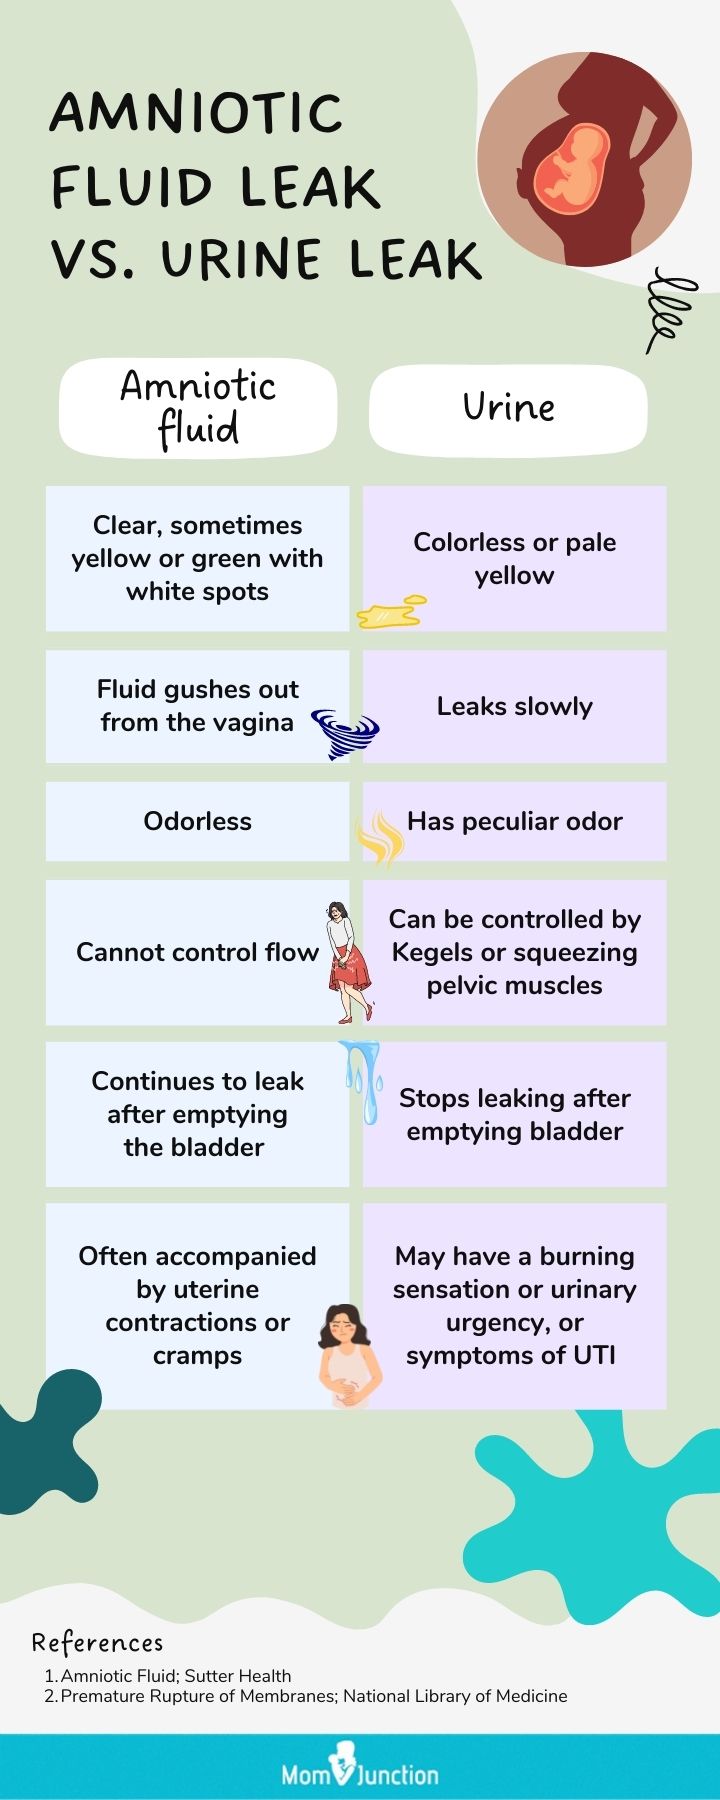

How To Recognize Leaking Amniotic Fluid And What To Do? MomJunction